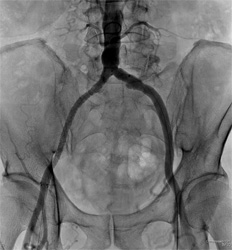

下肢動脈血管形成術

治療前   治療後

従来、放射線診断に用いられていた血管造影はCTやMRIの発展にともない、現在では主として治療目的のために行われています。この手法はIVR(インターベンショナル・ラジオロジー)と呼ばれています。

当院の血管造影室には、全身用にAlluraXperFD20、心臓血管造影用にはAlluraXperFD10/10(いずれもフィリップス社製)が導入され、フルデジタル化により再現性の高いデータを迅速に参照できるようになり、より精度の高い検査と治療を行っています。

この装置に大型複合モニターフレックスビジョンも組み合わされ、全身から末梢の小さな領域まで細かな情報を表示する事が可能です。また血管内超音波(IVUS)もDSA装置に組み込んであり、大動脈ステントグラフトから、四肢の血管病変まであらゆる領域で精度の高い治療が可能です。また、管球部分を回転またはスライドする事でCTのような横断画像を作る事も可能で、腫瘍に対する塞栓術を行なう際にも、正確な範囲を治療する事が可能となりました。